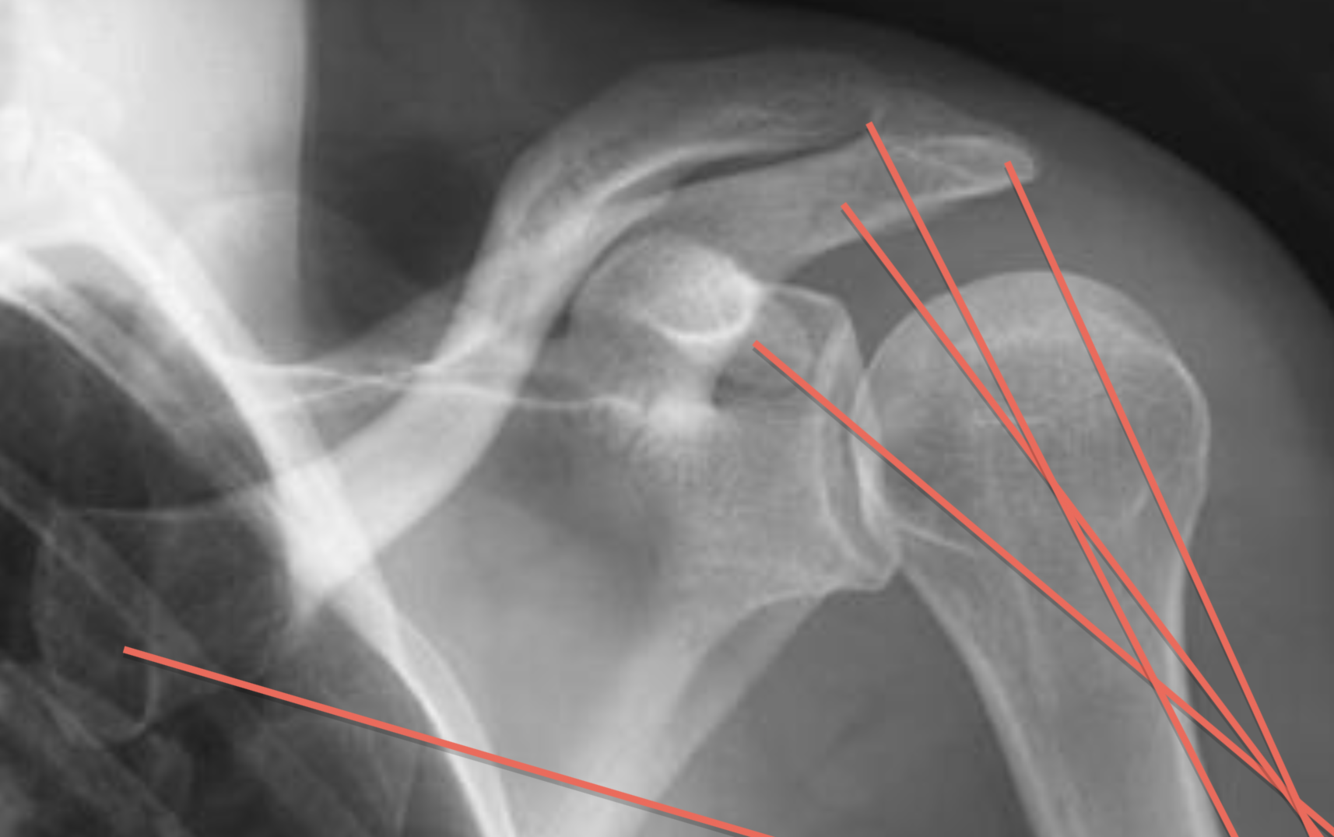

AP Internal Rotation - Shoulder

rotation int car le trochin médiale et tochiter plus lat

rot int de l”paule G car trochin et trochiter sont écarté

positionnnement articulation gléno huméral visible

on voit le processus coracoide G

épine

acrominon

glénoide G